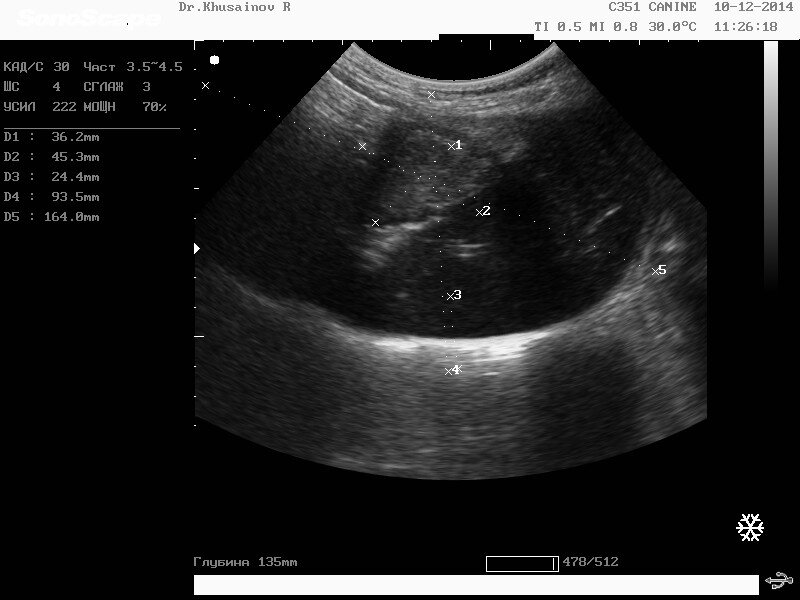

стерлитамак узи

Дружба 33 стерлитамак узи 75 фото